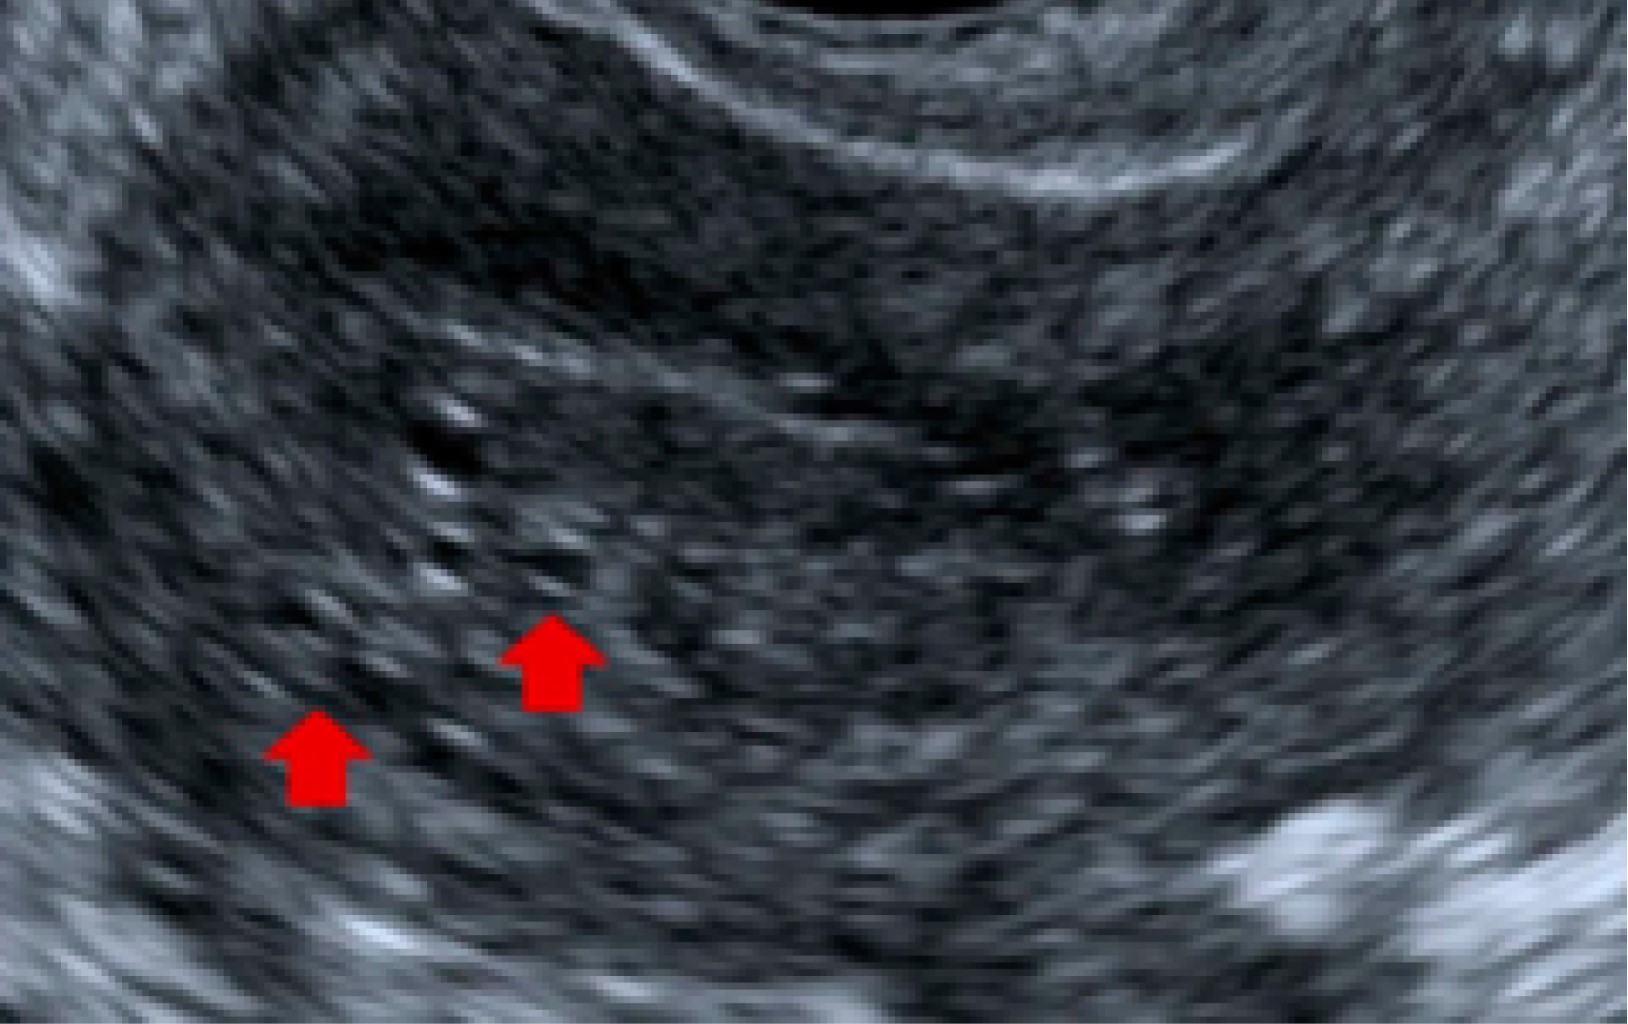

Para el uso de ultrasonido se recomienda un abordaje transvaginal, encontrando infiltración endometrial: con estriaciones ecogénicas y nódulos, quistes miometriales y divertículos "lollipop"; así como proliferación de músculo suave, ya sea de tipo focal o difuso con bordes en el miometrio. En cuanto a la vascularidad, mediante ultrasonido Doppler se observa aumento de la angiogénesis con vasos tortuosos. La mayor sensibilidad en el diagnóstico se logra con el uso de la resonancia magnética, en la que los hallazgos son similares a los observados en el ultrasonido;8 dentro de estas observaciones se entiende lo siguiente:9 en las imágenes T2 se observa alargamiento uterino con regiones más definidas y de baja intensidad con hiperplasia del músculo liso (zona de unión de más de 12 mm), quistes miometriales hiperintensos que reflejan regiones del tejido miometrial ectópico; con posible señal T1 intrínseca incrementada o con mayor sensibilidad para focos hemorrágicos. No existe recomendación de mejora con el medio de contraste, ya que no permite valorar o identificar la vascularización de la zona (Figura 2).

Figura 1